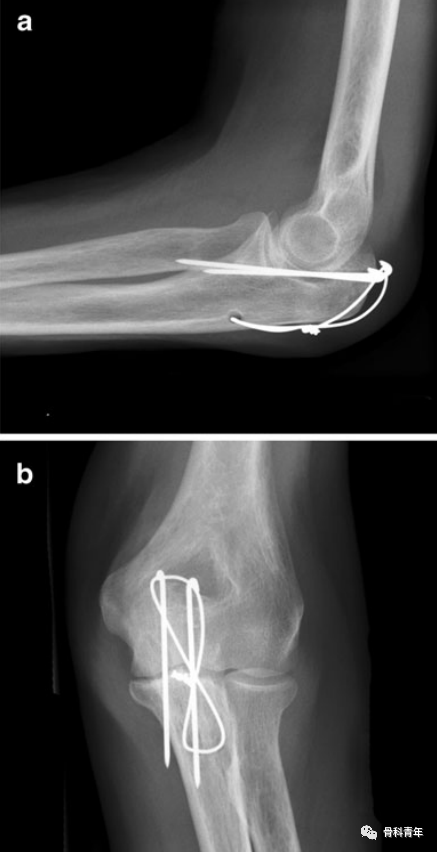

病例3:该患者X线显示克氏针向桡侧偏斜;克氏针过长。